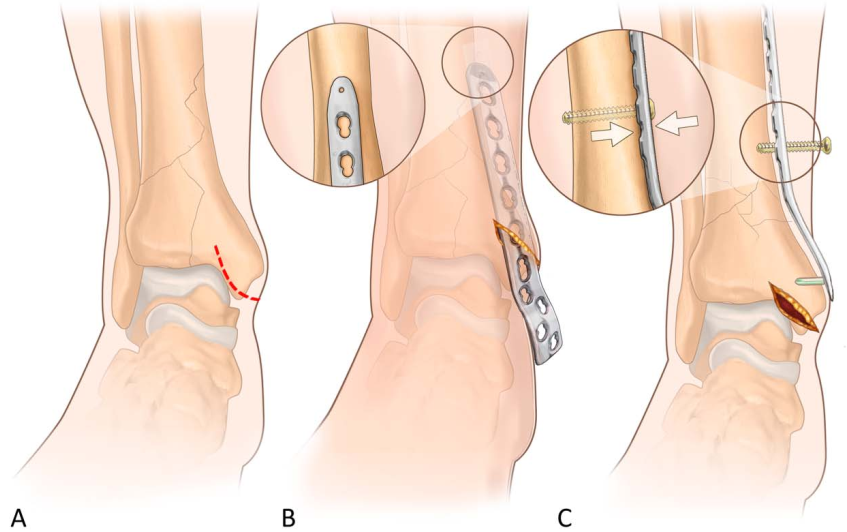

患者取仰卧位,切口始于踝关节远端4cm处,沿腓骨前缘向近端延伸至胫骨骨折最近端上方(图A)。切口深达腓骨前缘,注意保护腓浅神经。建议不先固定腓骨,以便通过移位骨折块改善胫骨的显露和复位。随后在腓骨前缘上方仔细钝性分离至骨间膜,用大型骨膜剥离器或手指分离骨间膜与前方骨筋膜室内容物之间的平面,将前方骨筋膜室肌肉向内侧牵开(图B),以保护与肌肉一同移动的神经血管束。在关节水平,识别腓骨上的前下胫腓韧带,沿其向内侧追踪至前外侧 Tillaux-Chaput骨折块(图C)。

将该骨折块(通常较大)向外侧翻转,可显露后关节面和后柱并进行复位。将关节面撬拨复位,通常按从后向前、从外到内的顺序进行解剖对位,用克氏针临时固定,可采用松质骨自体骨移植支撑复位后的关节面。后柱或外侧柱复位需进一步显露关节近端,可通过牵开前方骨筋膜室内容物实现。此时可复位腓骨,用小型接骨板固定(图D),在胫骨远端关节边缘近端小心放置带锁定螺钉的解剖型前外侧干骺端接骨板,经肌下沿胫骨外侧面向近端延伸,最后按常规方式仔细缝合软组织(图E)。